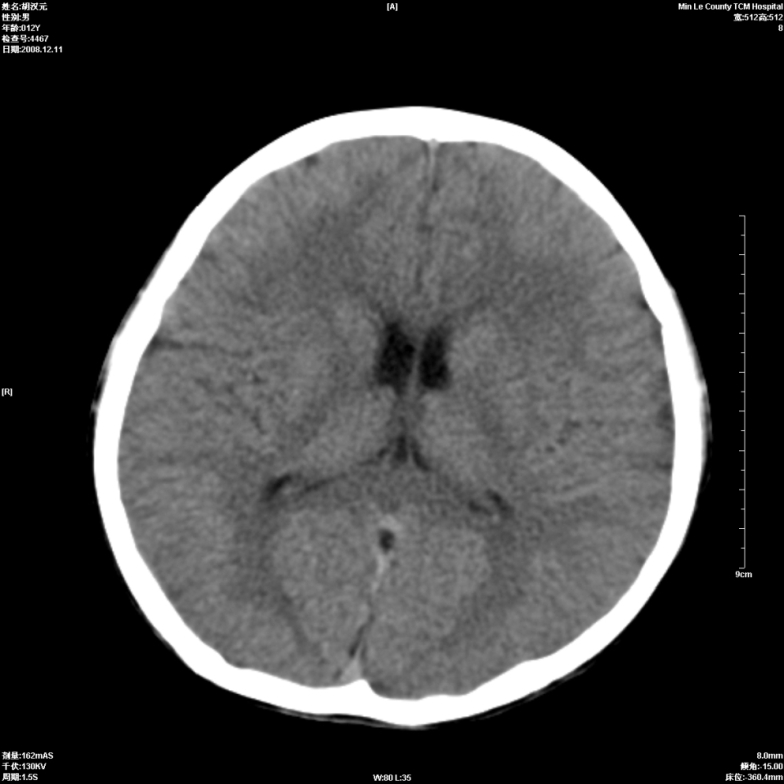

标题: PED1681:头疼发热约一周 [打印本页]

标题: PED1681:头疼发热约一周

颅脑未见确切异常。必要时进一步检查,如mri、脑脊液检查。

左侧基底节区腔梗?可以考虑吗?

颅脑ct轴位平扫颅内未见明确异常;建议必要时复查或行进一步检查。

颅脑ct轴位平扫颅内未见明确异常;